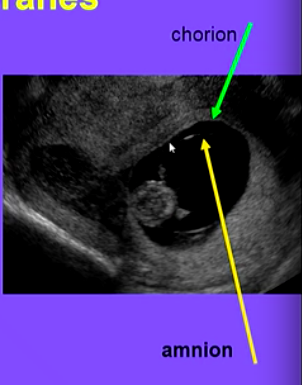

What are the membranes that are ruptured for labour?

The amnion and chorion. (strong and fused during pregnancy)

Therefore by manually trying to rupture/tear membranes ⇒ release PGs ⇒ clinically induce labour